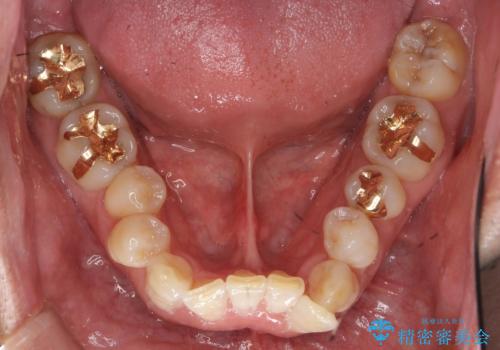

重度の叢生(歯並びのがたがた)のため、

①小臼歯抜歯でしっかりと歯並びを整える矯正治療

②前歯のセラミック治療を行いやすくするための補綴前矯正

患者様の「できるだけ短期間で治療を終わらせたい、セラミックが入れられたら良いので大がかりなことはしたくない」とのご要望により、3Dシミュレーションを何度も行い患者様とのコンサルを重ね、上顎左右犬歯と左下2を抜歯して②のプランである補綴前矯正(インビザライン)を行うことにしました。

寿命が長く機能的に重要な役目を果たす犬歯を抜くリスクや、矯正治療の仕上がりに限界があることをご理解頂いた上で治療を行っております。

親知らずの抜歯はご希望されなかったため行いませんでした。